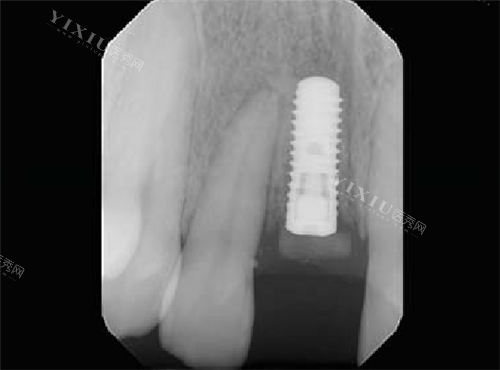

瑞士士卓曼iti种植牙植入后

在接下来的几天里,肿胀和疼痛逐渐减轻。我能明显感觉到口腔里的伤口在慢慢愈合。大约过了两周,我去医院进行了复查。医生检查后说,伤口愈合得非常好,种植体也很稳定。听到这个消息,我心里别提有多高兴了。

瑞士 ITI 亲水种植牙的愈合时间果然比普通种植体要短。在术后两个月左右,我就基本修养得差不多了。这期间,我能感觉到自己的饮食和说话都越来越正常,生活质量也大大提高了。